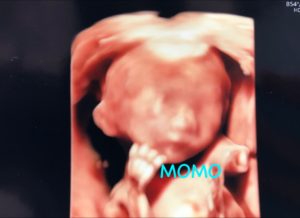

4D写真も貰いました。